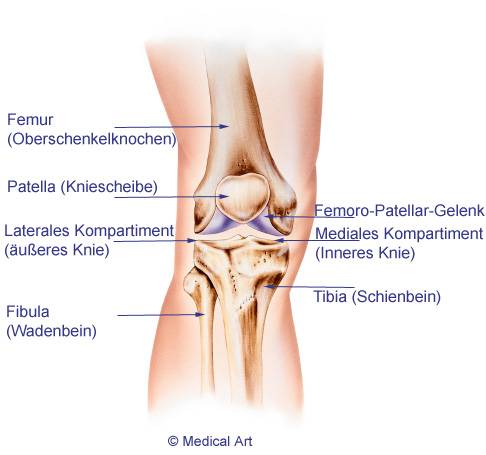

Die Femurkomponente der Knieprothese aus Metall bedeckt das untere Ende des Oberschenkels im Kniegelenk. Sie muss die paarigen, walzenförmigen Enden des Oberschenkels (Femurkondylen bzw. Oberschenkelrollen) im künstlichen Kniegelenk exakt nachformen. Vorne in der Mitte zwischen den Femurkondylen weist die Femurkomponente einen Spalt bzw. eine Vertiefung auf. Diese entspricht der patellaren Gleitrinne (Trochlea), welche die Kniescheibe in sich aufnimmt. So kann die Kniescheibe stabil gleiten, während das Kniegelenk sich beim Gehen beugt und streckt.

Die Schienbeinkomponente bedeckt das Schienbeinplateau, auf dem der Oberschenkel im Kniegelenk gleitet. Kreuzband und Meniskus fixieren und stützen das Kniegelenk. Auch die Tibiabasisplatte (Schienbeinkomponente) besteht in der Regel aus Metall. Um der von oben kommenden Metallkomponente des Oberschenkels eine Gleitpaarung zu bieten, ist sie bedeckt durch eine elastische, aber haltbare Kunststoffschicht aus Polyethylen. Die Schienbeinkomponente kann durch einen Stiel im Knochen verankert werden, um ihre Haltbarkeit zu verbessern.

Wenn die Kniescheibe auf ihrer Rückseite durch eine Patellaarthrose geschädigt ist, kann eine Gleitfläche aus Polyethylen ihre Gleitfähigkeit wiederherstellen. Diese Kniescheibenkomponente muss nicht bei jeder Knie-TEP verwendet werden. Ist das Gelenk zwischen Kniescheibe und Oberschenkelknochen (Femoropatellargelenk) noch intakt, kann die natürliche Kniescheibe belassen werden.

Das Kniegelenk wird häufig als Scharniergelenk missverstanden: ein Gelenk, das eigentlich nur eine Bewegungsrichtung erlaubt. Tatsächlich sind Beugen und Strecken des Beines die hauptsächlichen Bewegungsrichtungen des Knies. Das natürliche Kniegelenk erlaubt aber zudem andere Bewegungen, um seine Funktion optimal zu erfüllen. Die Gelenkpartner im Kniegelenk (Oberschenkelknochen und Schienbein) verschieben sich auch seitlich und nach vorne. Sie können sich bei manchen Bewegungen zudem rotierend gegeneinander verschieben. Ein reines Scharniergelenk würde dieser Bewegungsaufgabe des natürlichen Kniegelenks nicht gerecht werden.